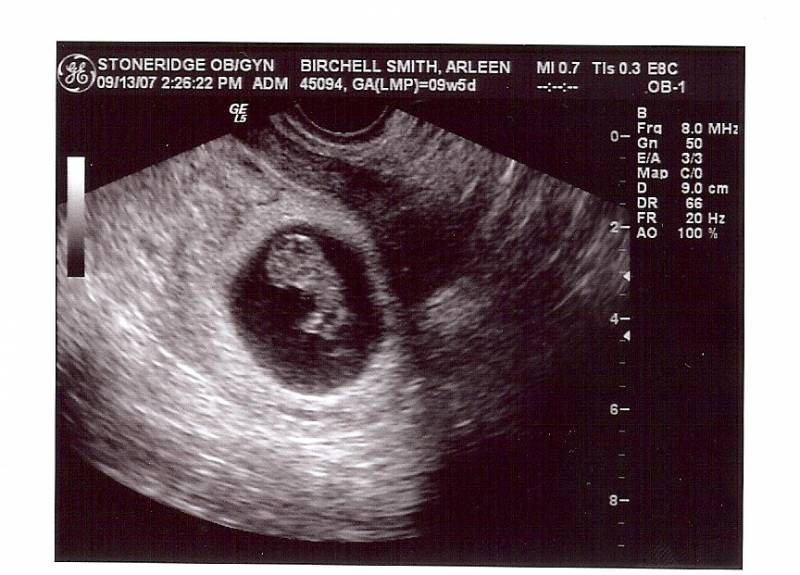

УЗИ на 9-й неделе беременности: фото.

На девятой неделе беременности плод продолжает активно развиваться, и врачи отмечают значительные изменения в его организме. В этот период длина эмбриона составляет около 2,5 см, и он начинает приобретать более четкие очертания. Формируются основные органы, такие как сердце, легкие и почки, а также начинается развитие нервной системы. Врачи подчеркивают, что в это время происходит активное деление клеток, что способствует росту и развитию тканей.

Пока еще не время ощущать удары сердца, но уже можно услышать его — на допплеровском аппарате во время ультразвукового исследования на 9-й неделе беременности вы сможете услышать сердцебиение вашего малыша!

На УЗИ слышно сердцебиение ребенка

На девятой неделе беременности развитие плода и ваши ощущения следующие: пока еще рано что-либо ощущать или слышать. Сердце вашего малыша уже достаточно сформировано и увеличилось до такого размера, что его биение можно зафиксировать с помощью допплера — портативного ультразвукового устройства, которое улавливает сердечные ритмы.

Не переживайте, если ваш врач пока не смог услышать сердцебиение вашего ребенка. Это может означать, что ваш маленький «скромняга» прячется в уголке матки, не позволяя допплеру уловить звук. В течение нескольких недель или на следующем визите этот удивительный звук сердцебиения, безусловно, станет слышен.